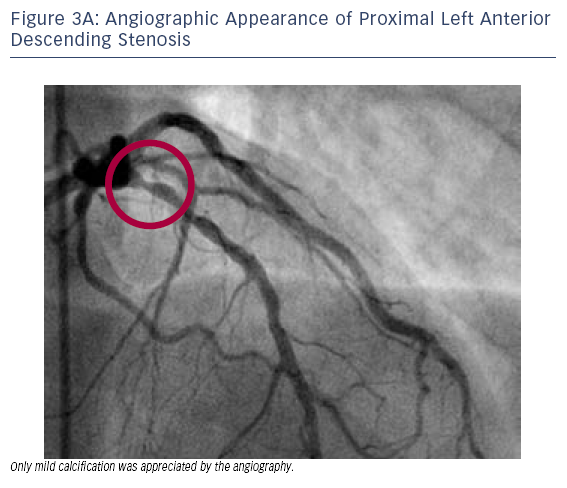

- Cardiac catheterisation revealed a segmental 70–80 % stenosis in the proximal LAD (Figure 3A) and total occlusion of the RCA. Only mild LAD calcification was appreciated based on the angiographic

appearance.